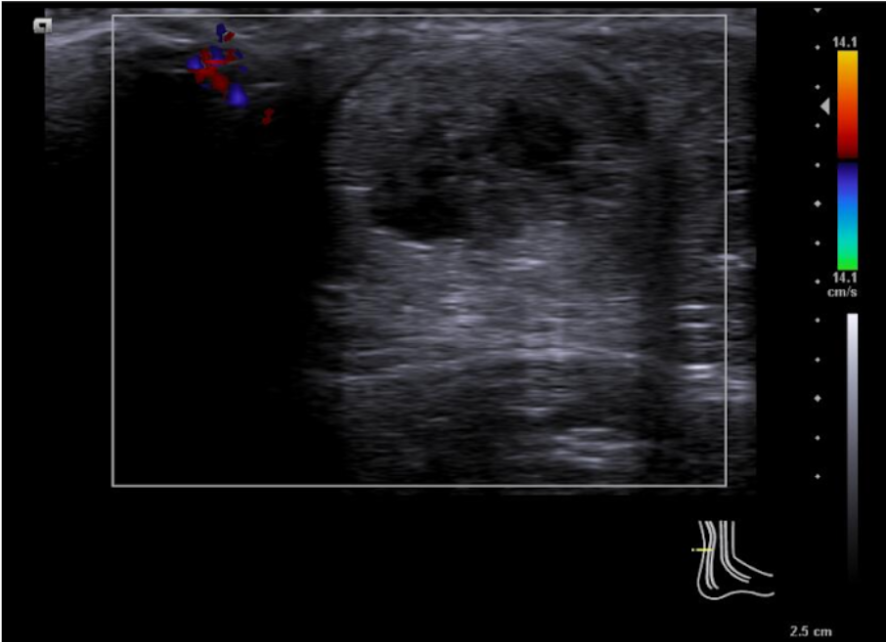

Se emplea sonda lineal L10-5v de forma longitudinal al tendón de aquiles, observando una zona anecoica en interfase del tendón a unos 7 cm de la inserción calcánea, con pérdida de continuidad del patrón fibrilar de las fibras tendinosas y aumento del grosor de este. No aumento de captación en Doppler.